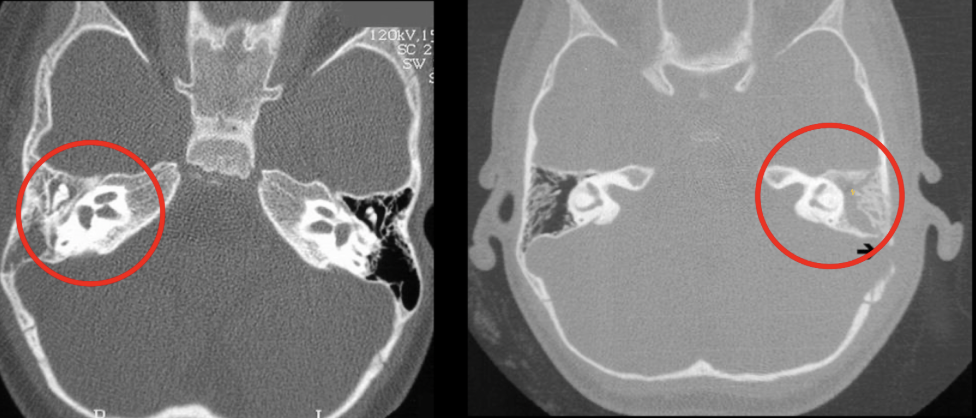

Dx de la siguiente imagen

Matoiditis

Clave en imagneología para dx de mastoiditis

Opacificación de celdillas mastoideas+ colección de líquido (pus o moco)

Si es crónico vemos efecto esclerodiploico que es mastoides osificada